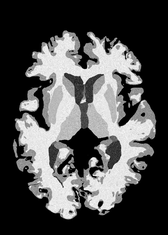

4.2 Registration to a 100 micron ex-vivo brain MRI volume

To showcase the efficacy of our method on real large scale images, we register a 250 in-vivo MRI image (Lüsebrink et al., 2017) to a 100 ex-vivo FLASH human brain volume (Edlow et al., 2019). This represents an inverse problem with more than 11.2B optimizable parameters (compared to 20M for clinical datasets), or 44.8GB of GPU memory. The entire problem does not fit on most GPUs, necessitating distributed multimodal registration. We optimize a composite transform - affine followed by a diffeomorphic mapping; details can be found in Section E.1. Multimodal deformable registration took 58 seconds on 8 NVIDIA A6000 GPUs, which is unprecedented at this resolution. Fig. 6 shows qualitative results, highlighting the ability to register highly detailed structures such as cerebellar white matter; these structures are not visible at macroscopic scales. The resultant advantages of performing registration at this scale can allow researchers to characterize the neuroanatomy at microscopic resolutions and allow morphometric analysis of cortical layers and subcortical nuclei among other structures.